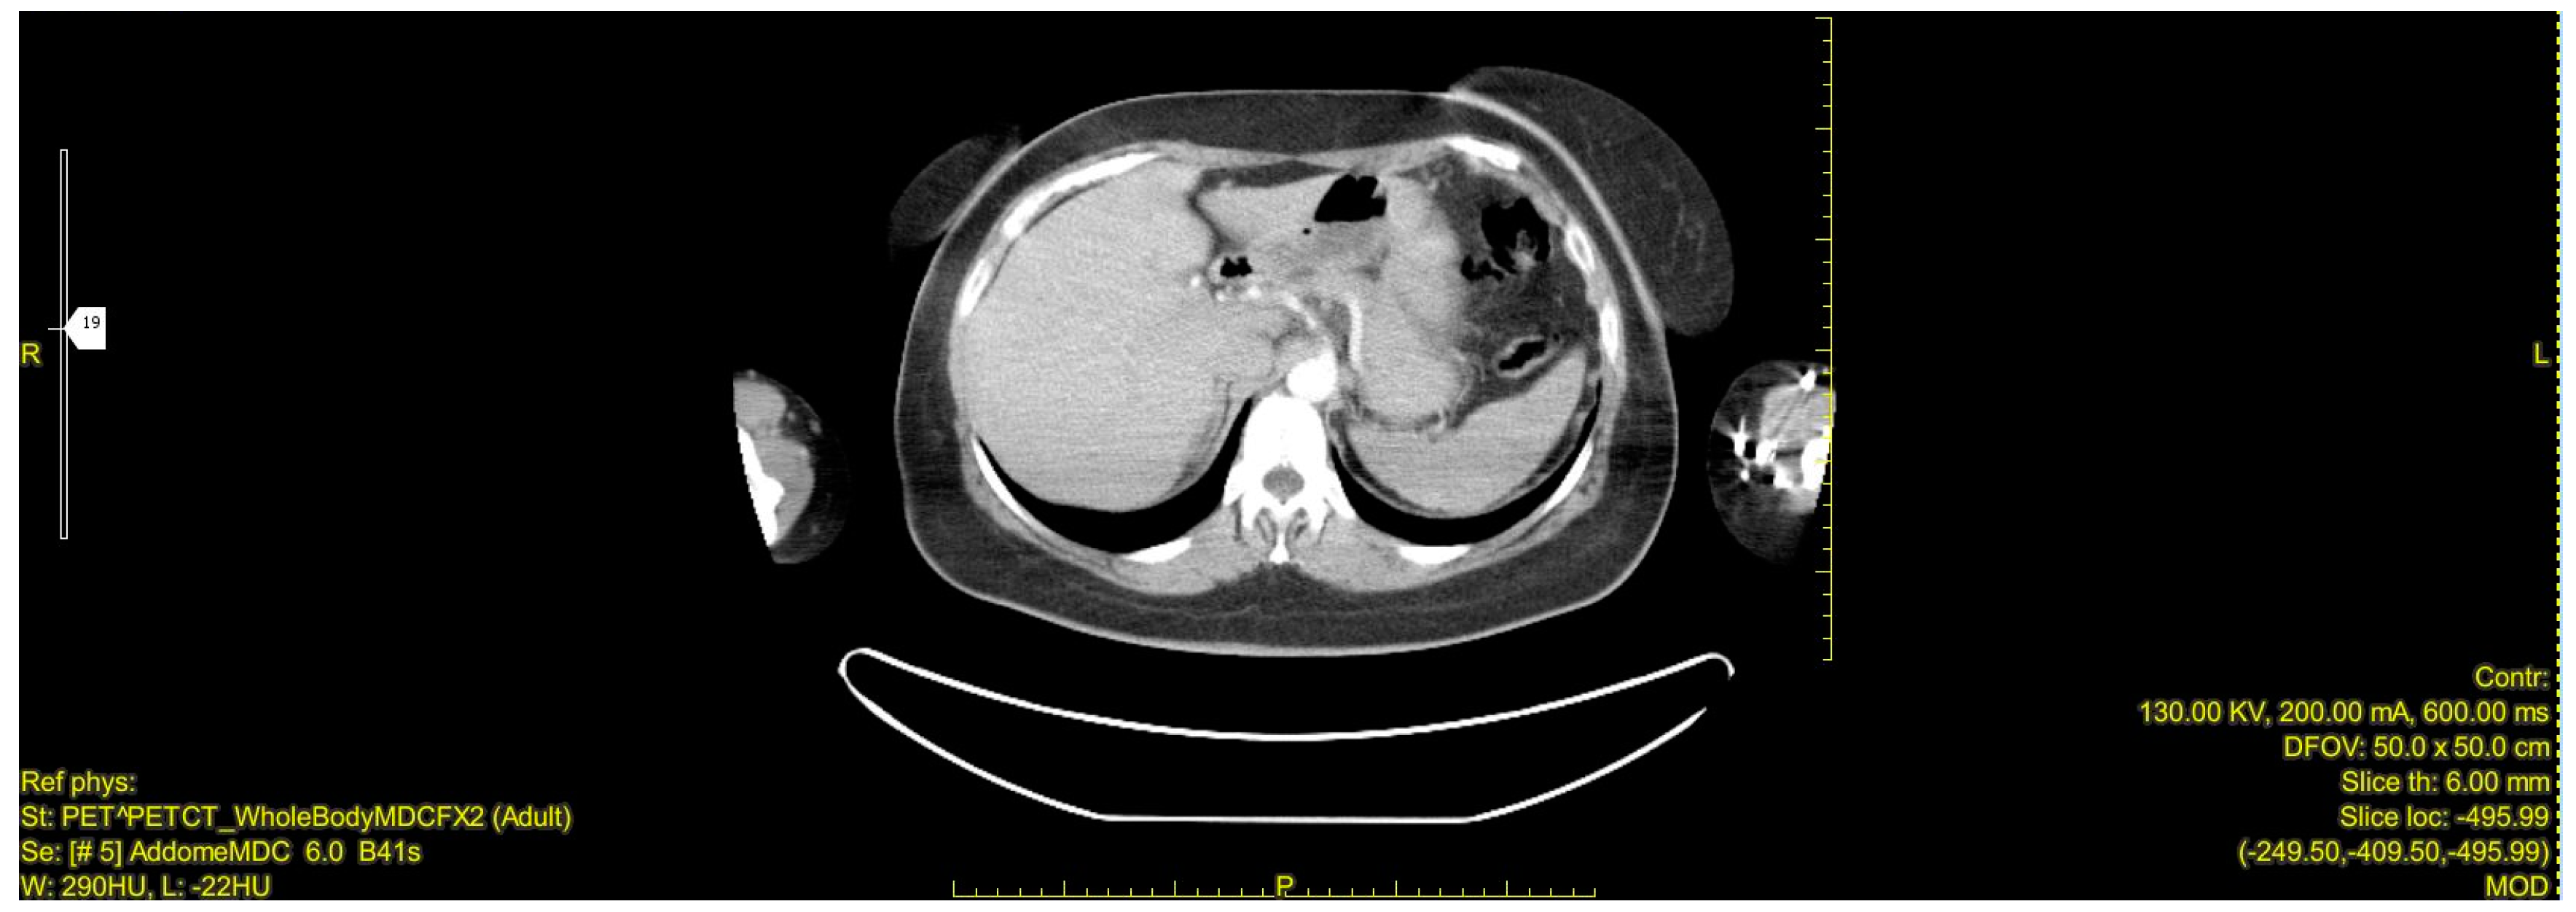

During the follow-up examination at 4 months post-surgery, a PET-CT scan without contrast conducted at another facility revealed a prominent focal hypermetabolic lesion in the hepatic segment V measuring approximately 51 × 44 mm with a SUV of 14.3, indicative of a secondary lesion. Additionally, osteolytic lesions were observed along the lateral aspect of the third rib on the right hemithorax (SUV max 3.5) and the inferior angle of the left scapula (SUV max 3.2), along with multiple bilateral pulmonary nodules (SUV max 1.2) [Figure 5, Figure 6 and Figure 7]. Hence, the aggressive metastatic dissemination of leiomyosarcoma underscores the imperative for a prompt reassessment of the treatment approach and the contemplation of intensified therapeutic interventions.

Figure 5.

Postoperative Abdominal CT: Non postoperative complications at the surgical site.

Figure 6.

PET-CT whole body: hepatic metastasis with a SUV of 14.3.

Figure 7.

Abdominal CT: hepatic metastasis identified with green arrows.